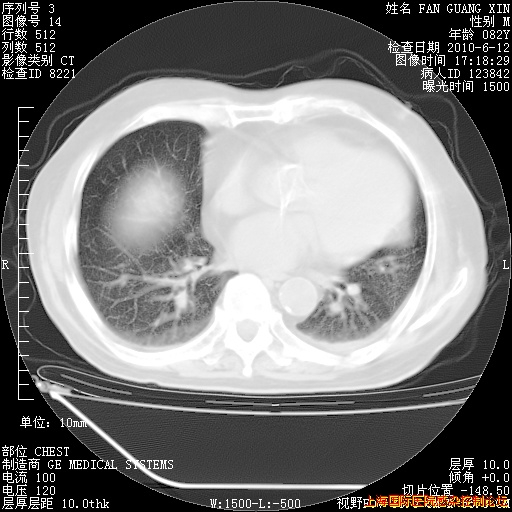

今天复查CT

今天CT

整整相隔30天的肺部CT好像有所好转啊。甲强龙减量第3天,需要观察体温。

海管,自昨日你和我通完话后,不知您岳父消化道症状有无缓解?体温怎样?阅读7.12日胸部ct,个人认为目前激素治疗是有效的,甲强龙减量是适宜的。因在抗痨治疗,需密切观察肝功、肾功能和血常规。不过,老年、长期住院和大量使用激素,很担心菌群失调发生